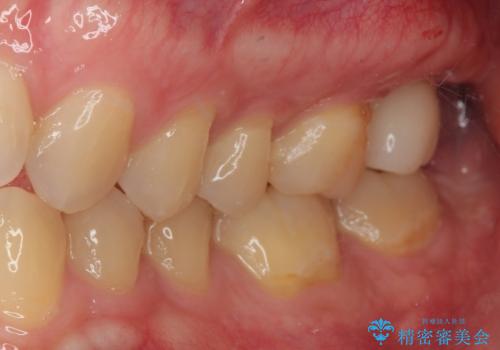

- 他院で虫歯治療の途中の歯を治療したいとのことで来院された患者様です。来院時特に症状もなく、根管治療途中の状態でした。レントゲン上でも大きい病変を認めました。治療方針として再度根管治療を行うか、抜歯をしてインプラントにする二つの方法をご提案しました。

咬み合わせが強く根管治療後の歯の破折のリスクや治療期間の観点からインプラント治療を行っていくこととなりました。